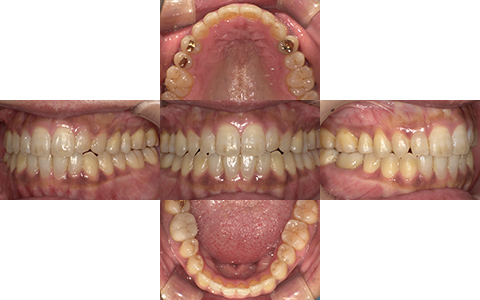

Before

After

| 施術内容 | 54歳女性 主訴:顎がガクガクする、前歯噛めない 詳細:インビザラインフルによる歯並びの改善 |

|---|---|

| 治療期間 | 1年4ヶ月 |

| 費用 | インビザフル880,000円+検査費27,500円 |

| リスク・副作用 | ・治療の初期段階では痛みや不快感が生じやすくなりますが、1週間前後で慣れます。 ・歯の動き方には個人差があるため、予想された治療期間より長くなる場合があります。 ・装置の使用状況や通院頻度など、患者さまの協力が不可欠で治療の結果や期間に影響します。 |